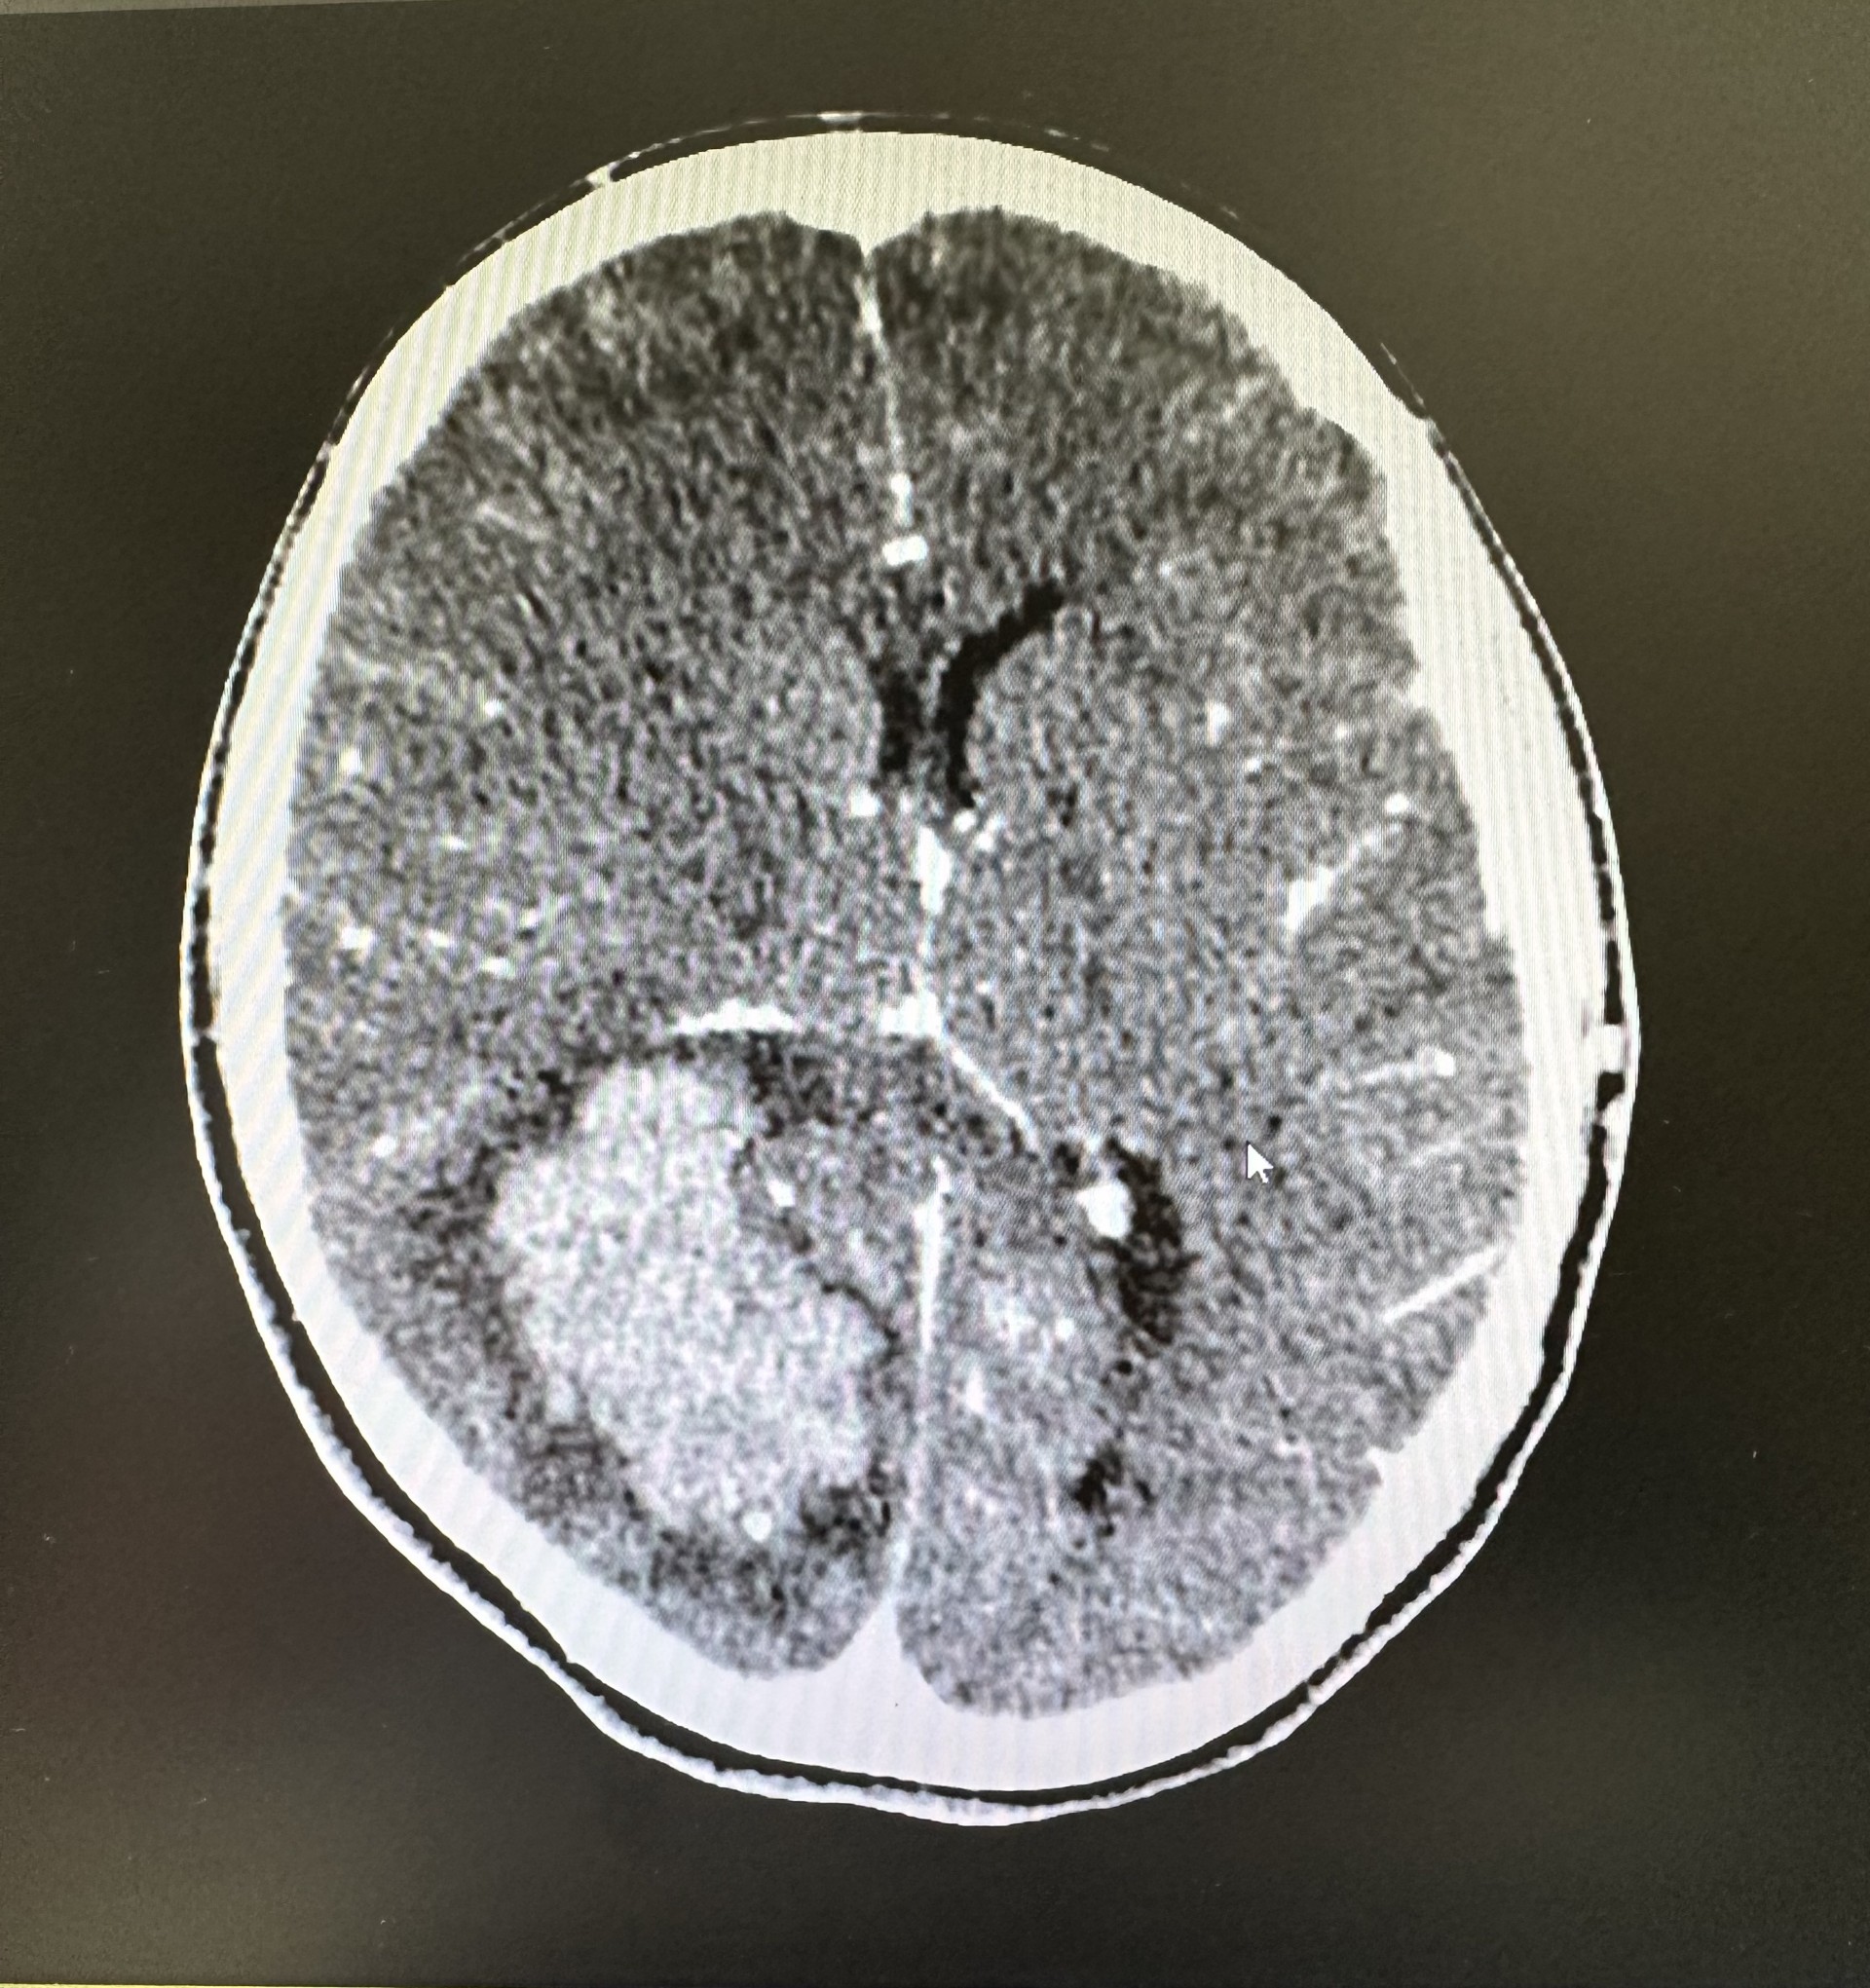

- Juicio clínico: La paciente es derivada al Servicio de urgencias hospitalarias. Se realiza TAC craneal simple y con contraste diagnosticando de hematoma intraparenquimatoso parietooccipital derecho. Se realizó posteriormente arteriografía, observando que dicho sangrado era secundario a una malformación arteriovenosa occipital parasagital hemisférica derecha.